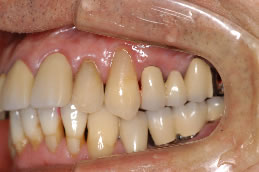

患者さんは48歳(女性)。全顎に義歯が装着されていましたが動かなくて、よく咬めるインプラント治療を希望の為来院。

写真5〜8はそれぞれ術前・後の左側口腔内写真とパノラマレントゲン画像です。

全顎にインプラントブリッジが装着され、審美的にセラミックで回復を施し、美しい笑顔が獲得された。さらに咀嚼機能も改善され患者さんも満足した症例である。

術後のパノラマレントゲン写真では、上顎10本、下顎8本のインプラントが埋入されている事が確認できる。